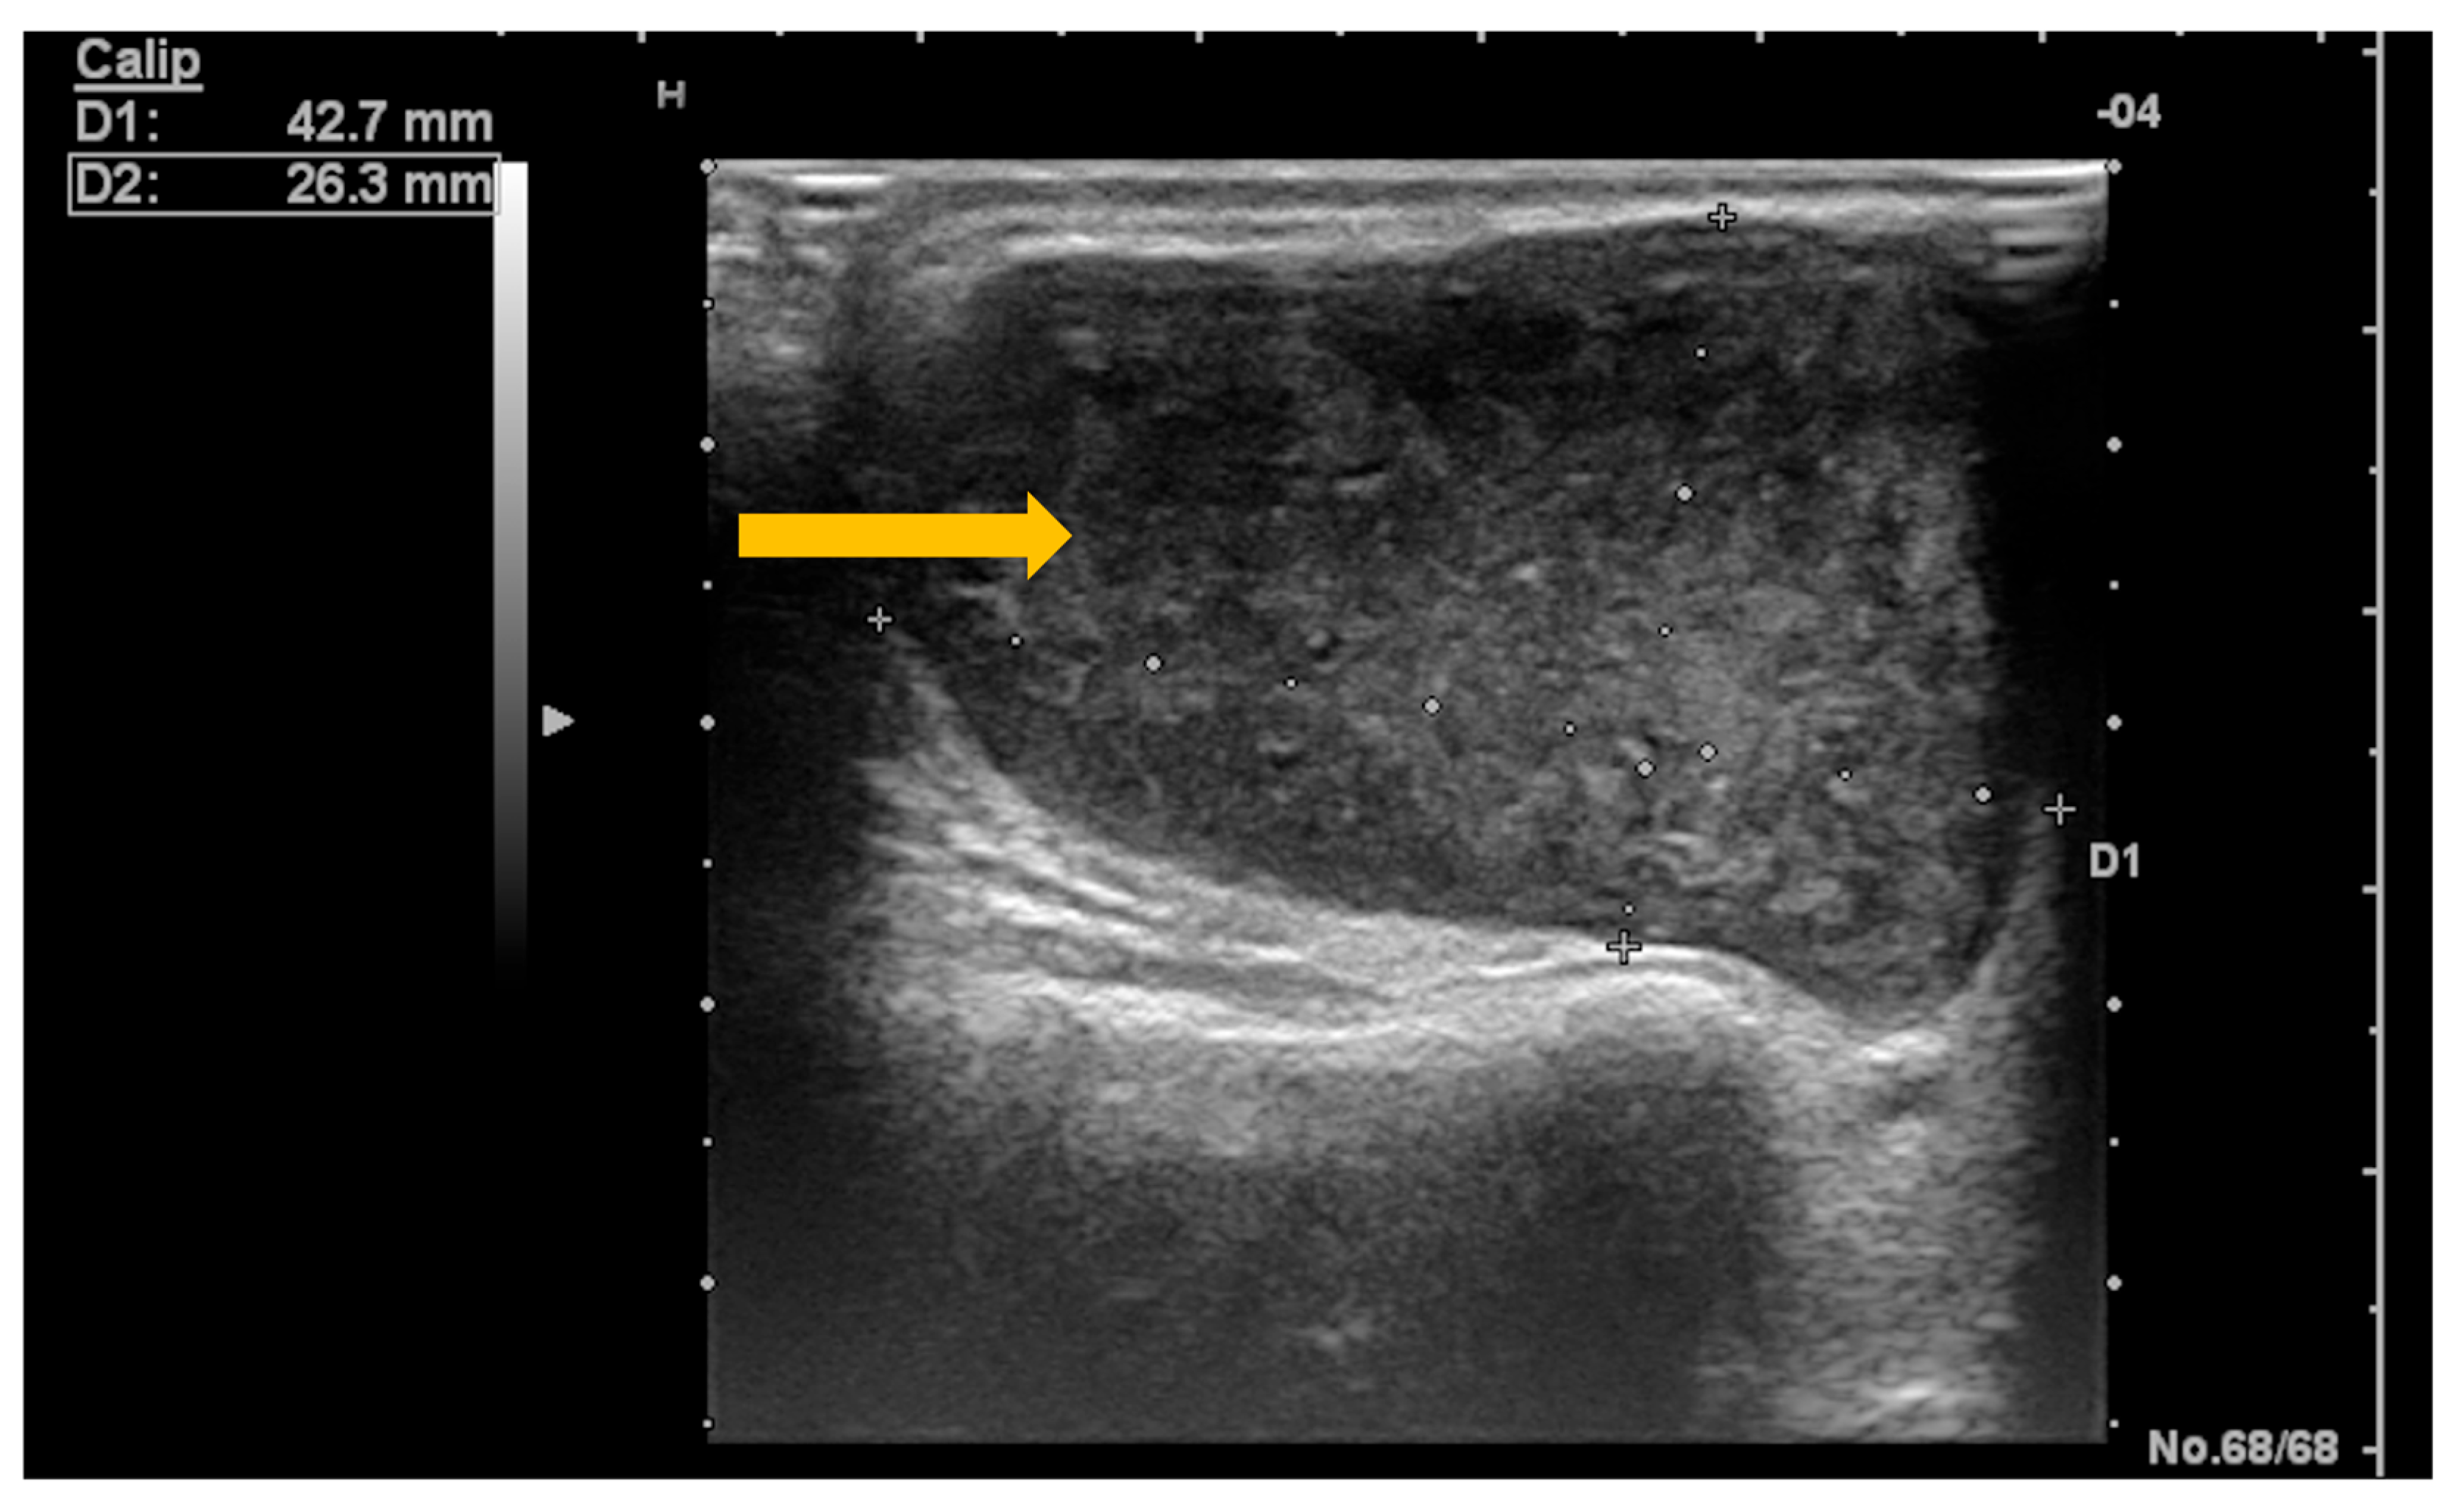

B lymphocytes play a central role in the pathogenesis of Sjögren’s syndrome through a process of chronic activation that contributes to immune system dysfunction [10]. This sustained stimulation is reflected in the increased risk of developing non-Hodgkin lymphoma, particularly the mucosa-associated lymphoid tissue (MALT) subtype [60,61,62]. Modern imaging techniques—ultrasonography and magnetic resonance imaging—are valuable for monitoring patients with Sjögren’s syndrome to enable early detection of lymphoma [63].

Ultrasonography is the imaging tool most frequently used in clinical practice due to its non-invasive nature, low cost, and wide availability [64]. Dynamic ultrasonographic evaluation of the salivary glands can identify a newly developed hypervascular, oval, relatively well-defined, hypoechoic nodular lesion with intrinsic hyperechoic septa and posterior acoustic enhancement (Figure 8 and Figure 9) [64,65]. At the same time, ultrasonography can be used to guide biopsies of lesions with suspicious imaging characteristics [63].

Figure 8. B-mode ultrasound of the parotid gland in a patient with Sjögren’s syndrome. Gray-scale (B-mode) ultrasound demonstrates a newly developed hypoechoic nodular lesion within the parotid gland (arrow), a finding suspicious for salivary gland lymphoma in the clinical context of Sjögren’s syndrome.